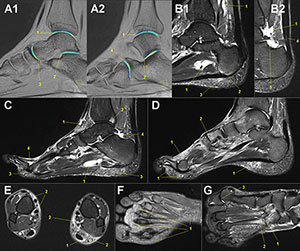

MRI investigations of the soft tissues and bones of the ultra-runners' feet showed a significant increase of the diameter of the Achilles tendon. "We found no relevant damage to bone or soft tissues in the 44 runners," Dr. Schütz said. "The human foot is made for running."